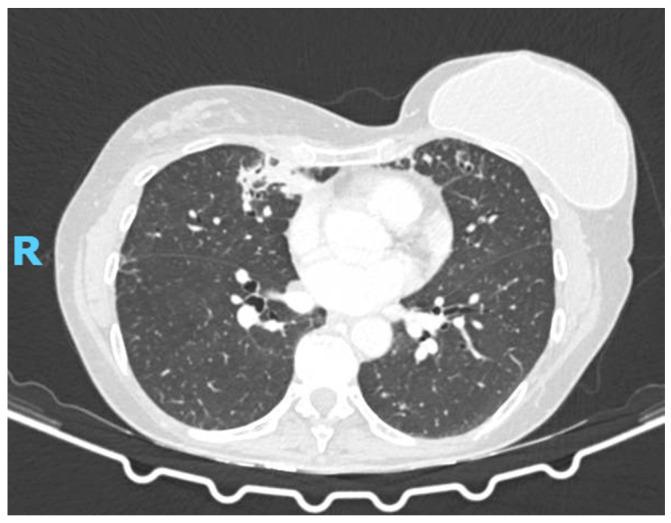

is a dematiaceous, thermotolerant, yeast-like fungus increasingly recognized as an opportunistic pathogen in chronic airway diseases. While commonly associated with cystic fibrosis, its clinical significance in non-cystic fibrosis bronchiectasis (NCFB) remains unclear. We report the case of a 66-year-old immunocompetent woman with a history of breast cancer in remission and NCFB, who presented with chronic cough and dyspnea. Chest CT revealed bilateral bronchiectasis with new pseudonodular opacities. Bronchoalveolar lavage cultures identified , along with and methicillin-sensitive . Given clinical stability and the absence of systemic signs, initial therapy included oral voriconazole, levofloxacin, doxycycline, and inhaled amikacin. Despite persistent fungal isolation on repeat bronchoscopy, the patient remained asymptomatic with stable radiologic and functional findings. Antifungal therapy was discontinued, and the patient continued under close monitoring. The patient exhibited clinical and radiological stability despite repeated fungal isolation, reinforcing the hypothesis of persistent colonization rather than active infection. This case underscores the diagnostic challenges in distinguishing fungal colonization from true infection in structurally abnormal lungs. In NCFB, disrupted mucociliary clearance and microbial dysbiosis may facilitate fungal persistence, even in the absence of overt immunosuppression. The detection of should prompt a comprehensive evaluation, integrating clinical, radiologic, and microbiologic data to guide management. Voriconazole is currently the antifungal agent of choice, though therapeutic thresholds and duration remain undefined. This report highlights the potential role of as an under-recognized respiratory pathogen in NCFB and the importance of a multidisciplinary, individualized approach to diagnosis and treatment. This case underscores the need for further research on fungal colonization in NCFB and the development of evidence-based treatment guidelines. Further studies are needed to clarify the pathogenic significance, optimal management, and long-term outcomes of in non-CF chronic lung diseases.

是一种暗色、耐热、酵母样真菌,越来越被认为是慢性气道疾病中的机会性病原体。虽然通常与囊性纤维化相关,但其在非囊性纤维化支气管扩张症(NCFB)中的临床意义仍不清楚。我们报告一例66岁免疫功能正常的女性病例,她有乳腺癌缓解病史和NCFB,表现为慢性咳嗽和呼吸困难。胸部CT显示双侧支气管扩张伴新的假结节状混浊。支气管肺泡灌洗培养物鉴定出了[具体真菌名称未给出],以及[其他微生物名称未给出]和甲氧西林敏感的[细菌名称未给出]。鉴于临床稳定且无全身症状,初始治疗包括口服伏立康唑、左氧氟沙星、多西环素和吸入阿米卡星。尽管在重复支气管镜检查时持续分离出真菌,但患者仍无症状,放射学和功能检查结果稳定。抗真菌治疗停药,患者继续接受密切监测。尽管反复分离出真菌,患者仍表现出临床和放射学稳定性,这强化了持续定植而非活动性感染的假说。该病例强调了在结构异常的肺部区分真菌定植与真正感染的诊断挑战。在NCFB中,黏液纤毛清除功能破坏和微生物生态失调可能促进真菌持续存在,即使在没有明显免疫抑制的情况下。[具体真菌名称未给出]的检测应促使进行全面评估,整合临床、放射学和微生物学数据以指导管理。伏立康唑目前是抗真菌治疗的首选药物,但治疗阈值和疗程仍不明确。本报告强调了[具体真菌名称未给出]作为NCFB中一种未被充分认识的呼吸道病原体的潜在作用,以及多学科、个体化诊断和治疗方法的重要性。该病例强调了对NCFB中真菌定植进行进一步研究以及制定循证治疗指南的必要性。需要进一步研究以阐明[具体真菌名称未给出]在非CF慢性肺部疾病中的致病意义、最佳管理和长期结局。